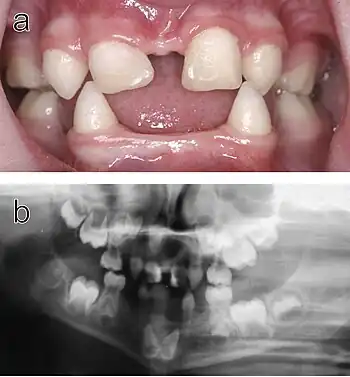

Ectodermal dysplasia is a rare but severe condition where the tissue groups (specifically teeth, skin, hair, nails and sweat glands) derived from the ectoderm undergo abnormal development. This is a diffuse term, as there are over 170 subtypes of ectodermal dysplasia. It has been accepted that the disease is caused by a mutation or a combination of mutations in certain genes. Research of the disease is ongoing, as only a fraction of the mutations involved with an ectodermal dysplasia subtype have been identified.[10]

Hypohidrotic ectodermal dysplasia (HED) is the most common subtype of the disease. Clinical cases of patients with this condition display a range of symptoms. The most relevant abnormality of HED is hypohidrosis, the inability to produce sufficient amounts of sweat, which is attributed to missing or dysfunctional sweat glands. This aspect represents a major handicap particularly in the summer, limits the patient's ability to participate in sports as well as his working capacity, and can be especially dangerous in warm climates where affected individuals are at risk of life-threatening hyperthermia. Facial malformations are also related to HED, such as pointed or absent teeth, wrinkled skin around the eyes, a misshaped nose along with scarce and thin hair. Skin problems like eczema are also observed in a number of cases.[11] Most patients carry variants of the X-chromosomal EDA gene.[12] This disease typically affects males more severely because they have only one X chromosome, while in females the second, usually unaffected X chromosome may be sufficient to prevent most symptoms.